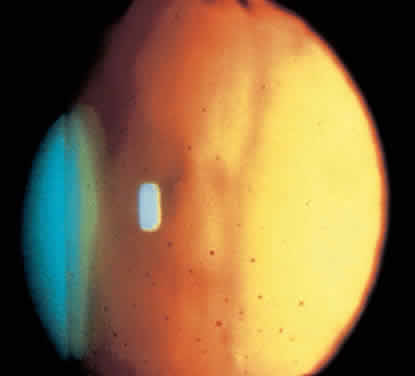

Fig. 7. Retroillumination of an eye with Fuchs' heterochromic iridocyclitis reveals diffuse distribution of keratic precipitates.

Chronic, mild anterior chamber cell and flare is common.124 Keratic precipitates are characteristically small, round, or stellate, with fine filaments between them (Fig. 6).121 Unlike other inflammatory conditions, they are distributed over the entire endothelium (Fig. 7).121 The anterior chamber angle is open. Inflammatory synechiae rarely develop spontaneously121 but may arise after cataract surgery.132 Neovascularization of the angle may occur (Fig. 8),22,123 but neovascular glaucoma is rare.133 Angle vessels are extremely fragile and have been reported to bleed with minor trauma such as gonioscopy,134 applanation tonometry,125 or Honan balloon application.135 Significant intraoperative hemorrhage is unusual,136 but minor bleeding may occur after a paracentesis, resulting in a discrete column of blood in the opposite angle (Amsler's sign).137 Ingeneral, angle abnormalities do not correlate well with the presence or severity of glaucoma.119